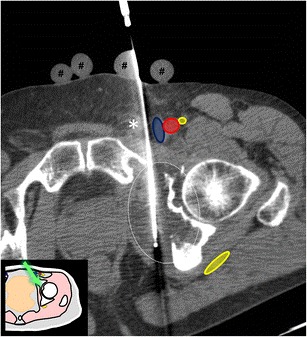

Фото: Трепан-биопсия новообразования под КТ-навигацией

С целью постановки диагноза опухоли кости рекомендовано применение трепан-биопсии (с помощью специального устройства и биопсийной иглы через прокол кожи и окружающих опухоль тканей производят забор столбиков ткани опухоли) и инцизионной биопсии (через разрез кожи и окружающих тканей удаляется фрагмент опухоли). При выполнении трепан-биопсии применяют различные способы навигации: ультразвук, рентгенография, компьютерная томография.

При выполнении биопсии, как и при любой инвазивной процедуре, существуют определенные риски для здоровья, их стоит обсудить с лечащим врачом.